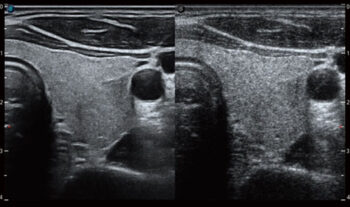

Шинэ үеийн μ-Scan+ нь B горим болон 3D/4D хэлбэрээр хийгдсэн бөгөөд эд, эрхтэнийг ялгахын тулд илүү нарийн зохион бүтээгдсэн. Энэ нь толбыг багасгахаас гадна зургийн жигд байдал, ирмэгийн тасралтгүй байдлыг сайжруулж, жинхэнэ нарийвчилсан танилцуулга, гэмтлийн дүрслэлийг сайжруулдаг.

Өндөр үр дүнтэй шүүлтүүрийн технологийг ашигласны ачаар SR-Flow-ийн тусламжтайгаар цусны урсгал болон эдийн дохиог ялгах нь илүү хялбар байдаг. Энэ нь өндөр мэдрэмжтэй, тод, динамик Доплер дүрслэлийг идэвхжүүлэхийн зэрэгцээ удаан урсгалыг илрүүлэх бодит туршилтыг баталгаажуулдаг.

Micro F нь хэт авиан дахь харагдах урсгалын хүрээг өргөжүүлэх, ялангуяа жижиг судасны гемодинамикийг дүрслэн харуулах шинэлэг аргыг санал болгодог. Ойролцоох эд эстэй харьцуулахад цусны урсгалын нарийвчилсан зураглал нь гэмтэл, хавдрыг үнэлэх оношлогооны найдвартай байдлыг өгдөг.